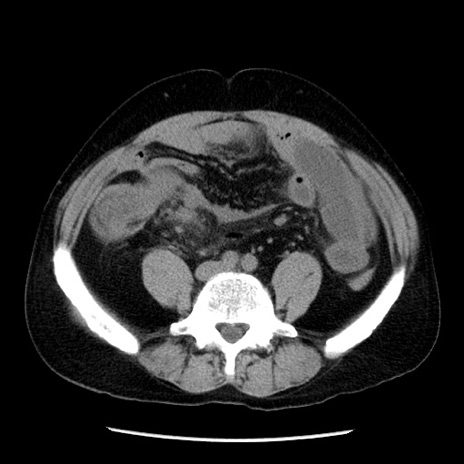

症例29(横断像)

【症例】40歳代男性

【現病歴】2日前から胃痛あり。徐々に周期的な激痛に変化した。本日になっても激痛があるため受診。

【身体所見】意識清明、BT 38-39℃台あり、腹部:膨満、やや硬、右下腹部に圧痛あり。

【データ】WBC 8500、CRP 23.26